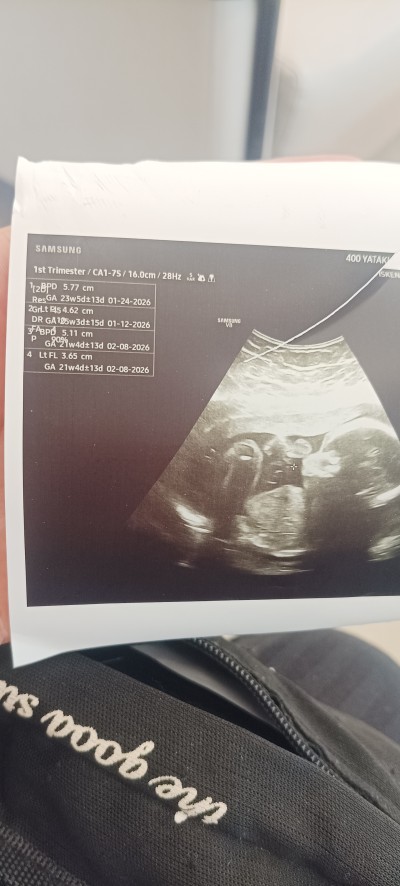

Sevgili hamileler anneler sor um bu aslında

yani bu haftalarda bu ölçümler normal mi

yapay zekaya da sordum ortalama olarak normal falan diyor ama zaten üst üste binmiş gibi ben bir şey anlamadım

doktor da hiçbir yorum yapmadı sadece ölçümleri söyledi daha sonra detaylı ultrason zamanın gelmiş hemen randevu al git dedi

başka hiçbir şey söylemedi öyle bir yüz ifadesi ilgisizliği vardı ki korkudan bir şey de soramadım

Gebelik haftası 22+3 ortalama olarak

Zaten 22 haftalıkmışsınız ölçümlerde aynı civarda sorun ne anlayamadım

Bi an önce randevu al demesinin sebebi ayrıntılı ultrason haftan geçiyor canım o yüzden,23 haftaya kadar yapılıyor ya o yüzden bi an önce al demiş.ufak tefek ölçüm farkları önemsiz